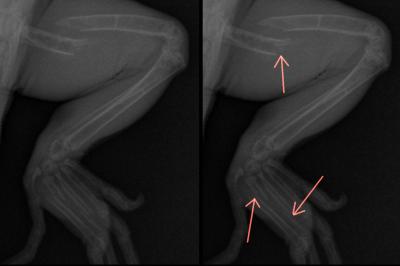

Pacient na fotkách je Charlienka - samička leguána. V jejím případě bylo hlavní příčinou onemocnění zadržení folikulů. Zárodky vajíček, které se nepřemění na vajíčka a stále jen rostou a rostou odebírají tělu enormní množství živin a minerálů, včetně vápníku a vitamínu D. Druhým faktorem byl nedostatečný zdroj UVB záření, umístěný příliš vysoko (většina komerčně prodávaných UVB zářivek by měla být maximálně 20 cm vysoko). RTG vyšetření odhalilo fraktury (zlomeniny zaprstních kůstek a kosti stehenní ukazují růžové šipky).